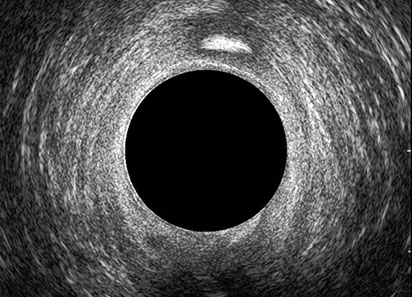

L’ecografia transanale è un esame diagnostico per immagini che consiste nell’introduzione di un trasduttore ad ultrasuoni. Le immagini qualitativamente migliori del canale anale sono ottenute usando un trasduttore rotante, montato in un manipolo rigido, che fornisce un’immagine a 360°. Con le apparecchiature più moderne è anche possibile ottenere immagini tridimensionali.

L’ecografia transanale permette di distinguere la sottomucosa che riveste il canale anale, lo sfintere anale interno, e lo sfintere anale esterno.

Le principali indicazioni all’esecuzione di tale esame sono lo studio dell’integrità delle strutture muscolari nei casi di incontinenza fecale, lo studio topografico dei processi settici perianali (ascessi e fistole) e lo studio dei processi proliferativi epiteliali (carcinoma anale).